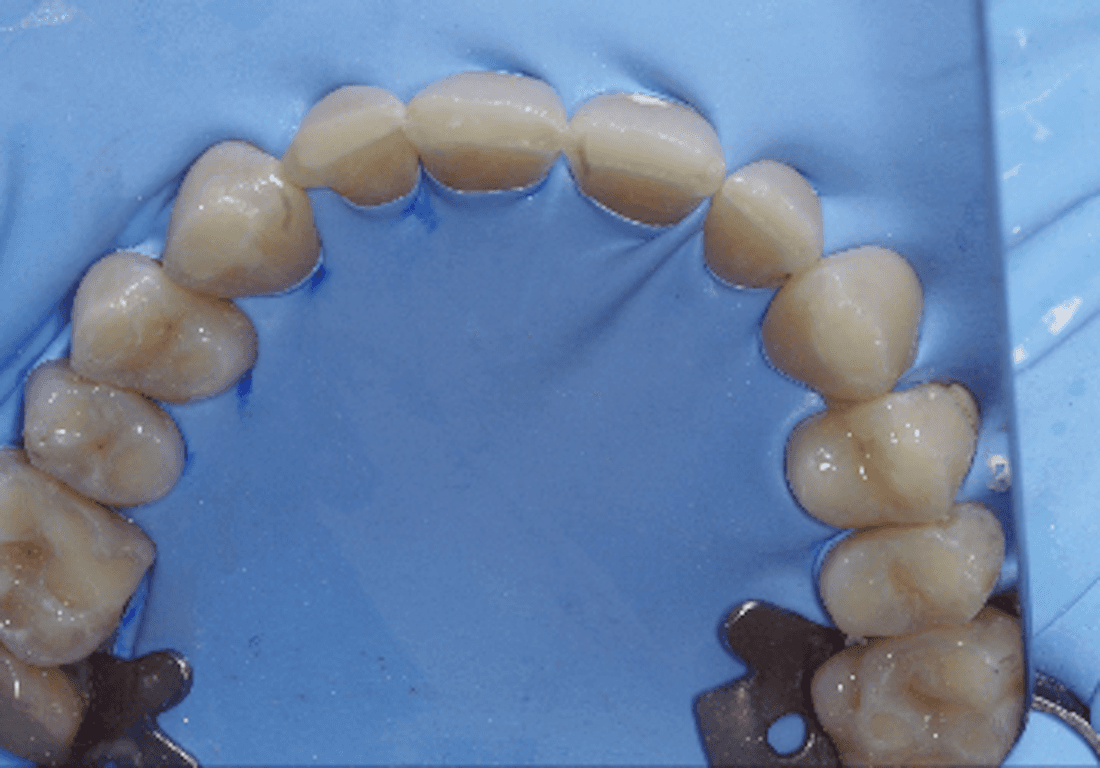

Sports drinks have among the highest acid concentration of all of our foods and drinks and these acids erode the teeth in a distinctive manner. These teeth all have eroded with this typical pothole appearance that accelerates the erosion, as now there's no enamel in these holes to resist wear.